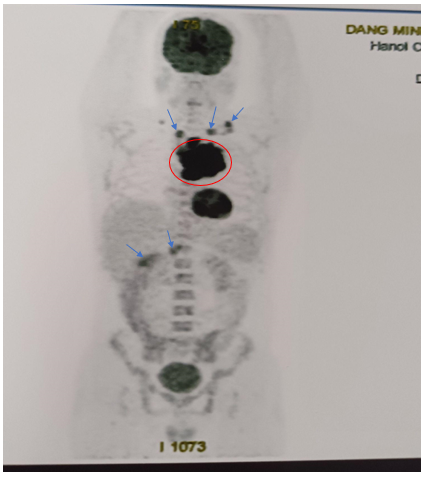

-         Hình ảnh chụp PET/CT đánh giá giai đoạn trước điều trị (tháng 5/2024)

·        Hạch nền cổ, thượng đòn 2 bên, lớn nhất ~ 28x18mm (SUVmax: 10.47).

·        Khối lớn ở trung thất trước, lệch trái kích thước ~84x109x90mm, phá hủy xương ức,cung trước xương sườn 3 trái, thành ngực trước trái, xâm lấn quai động mạch chủ (SUVmax: 17.88).

·        Vài hạch trung thất, lớn nhất 14x17mm (SUVmax: 3.17). Hạch rốn gan, hạch bẹn. Tăng nhẹ chuyển hóa FDG lan tỏa ở hệ thống xương.

Hình 2: Hình ảnh tăng chuyển hoá FDG ở nhiều vị trí khối lớn ở trung thất trước, hạch cả ở trên và dưới cơ hoành, tăng FDG lan tỏa hệ thống xương.

·        Huyết tủy đồ: Hình ảnh tủy tăng sinh. Không gặp tế bào di căn. Không thấy tăng lympho.